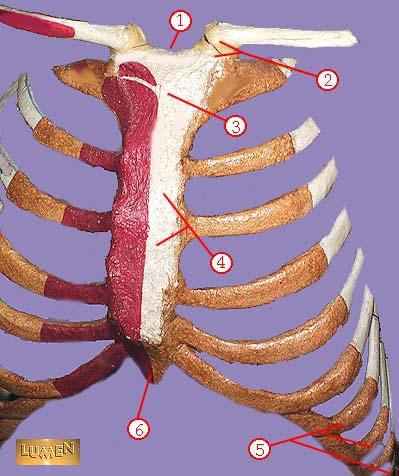

RIBS

THE BONY THORAX IS COMPOSED OF THE STERNUM, RIBS,AND THORACIC VERTEBRAE

THORACIC CAGE

HOW MANY RIBS

24 12 ON EACH SIDE

HOW MANT PAIRS OF RIBS ARE THERE

12 PAIR

RIB PAIRS 1-7

TRUE RIBS

RIB PAIRS 8-12

FALSE RIBS`

RIB PAIRS 11-12

FLOATING RIBS

ATTACH TO THE VERTEBRA AND ATTACH TO THE BREAST BONE

TRUE RIBS

HOW MANY TRUE RIBS DO YOU HAVE

14

HOW MANY FALSE RIBS DO YOU HAVE

10

ATTACH TO THE VERTEBRA AND DO NOT ATTACH

FALSE RIBS

A TYPICAL FLAT BONE IS THE RESULT OF THE FUSION OF THREE BONES..

THE STERNUM

FORMS THE BULK OF THE STERNUM

GLADIOLUS AKA BODY

WHAT IS THE CORRECT NAME FOR #1

sternal notch

WHAT IS THE CORRECT NAME FOR #2

sternoclavicular joint

WHAT IS THE CORRECT NAME FOR #3

manubrium

WHAT IS THE CORRECT NAME FOR #4

body of sternum GLADIOLUS

WHAT IS THE CORRECT NAME FOR #5

false ribs

WHAT IS THE CORRECT NAME FOR #6

xiphoid process